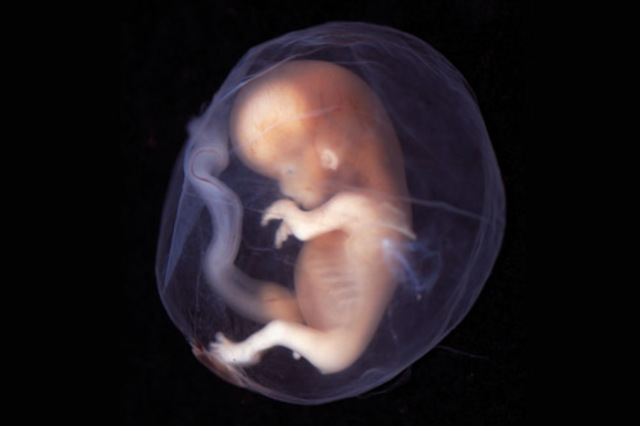

Hacia el final de esta semana,el cuerpo estará formado, así como todos sus órganos, y terminará el periodo embrionario. Dejará de ser un embrión para convertirse en feto. En esta semana, crecen os dedos de las manos y de los pies. La cabeza es desproporcinalmente grande y constituye la mitad del embrión. La región del cuello de ha formado. Su crecimiento en el útero se ve facilitado por un cuerpo más flexible; su esqueleto no tiene huesos, sino cartílagos.